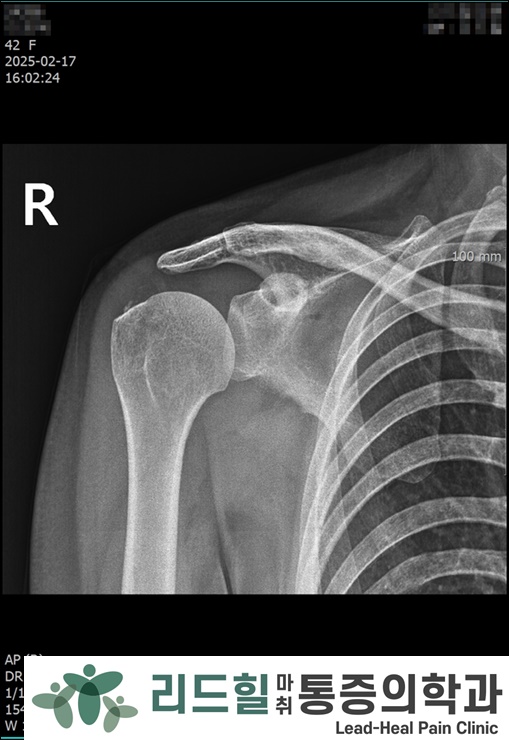

📸 3차 시술 후 X-ray

석회 크기는 줄었지만, 일부 잔존 석회가 보였습니다.

그러나 mass effect는 완전히 사라진 상태였습니다.

그래서 추가 시술 없이

체외충격파치료와 스트레칭 위주로 관리했습니다.